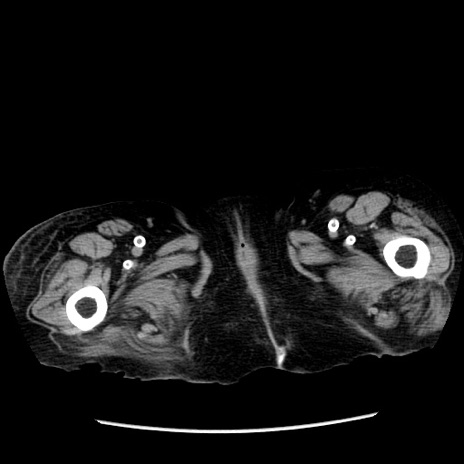

症例14(横断像)

【症例】 90歳代女性

【主訴】 腹痛・嘔吐

【現病歴】今朝から左側腹部痛を認めた。 経過観察していたが、嘔吐を認めたため来院。

【既往歴】 子宮癌術後

【身体所見】 意識清明、BP 127/54mmHg、P 98bpm Sp02 95%(RA)、BT 35.8°C、腹部平坦・軟腸ぜん動音聴取良好、右下腹部圧痛(+) 反跳痛なし

【データ】WBC 9800、CRP 0.46